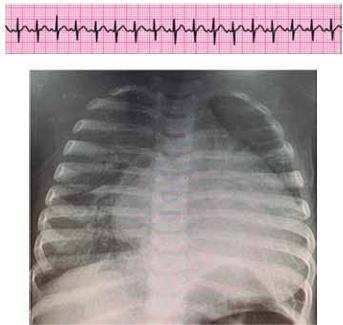

Em um serviço de emergência, lactente de 6 meses e admitido com sinais rebaixamento do nível de consciência, sudorese e palidez cutânea há, aproximadamente, 2 horas. Mãe refere que notou início dos sintomas após realizar inalação com salbutamol, prescrita por suposta bronquiolite (sic). Ao exame físico, criança em mau estado geral, pálida, FC = 220 bpm, pulsos finos, tempo de enchimento capilar de 5 segundos, PA = 64 x 33 (43) mmHg, FR = 60 ipm, sem alterações na ausculta pulmonar. Ao ser monitorizado obtém-se o ritmo cardíaco a seguir.

Enunciado 4584206-1

(Arquivo pessoal; imagem usada com autorização)

Assinale a alternativa que contenha a conduta mais adequada para o caso, de acordo com as melhores práticas segundo o PALS (Pediatric Advanced Life Support).